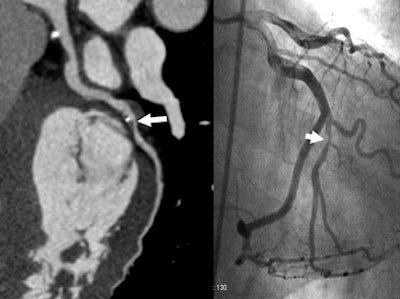

| A 45-year-old male with elevated risk factors and indeterminate exercise stress testing. CTA effective dose using PGA technique was 2.44 mSv. Curved multiplanar reformatted image (left) depicts a stenosis of the inferior branch of the second obtuse marginal coronary artery (OMB2). This was confirmed by conventional coronary angiography (right). |